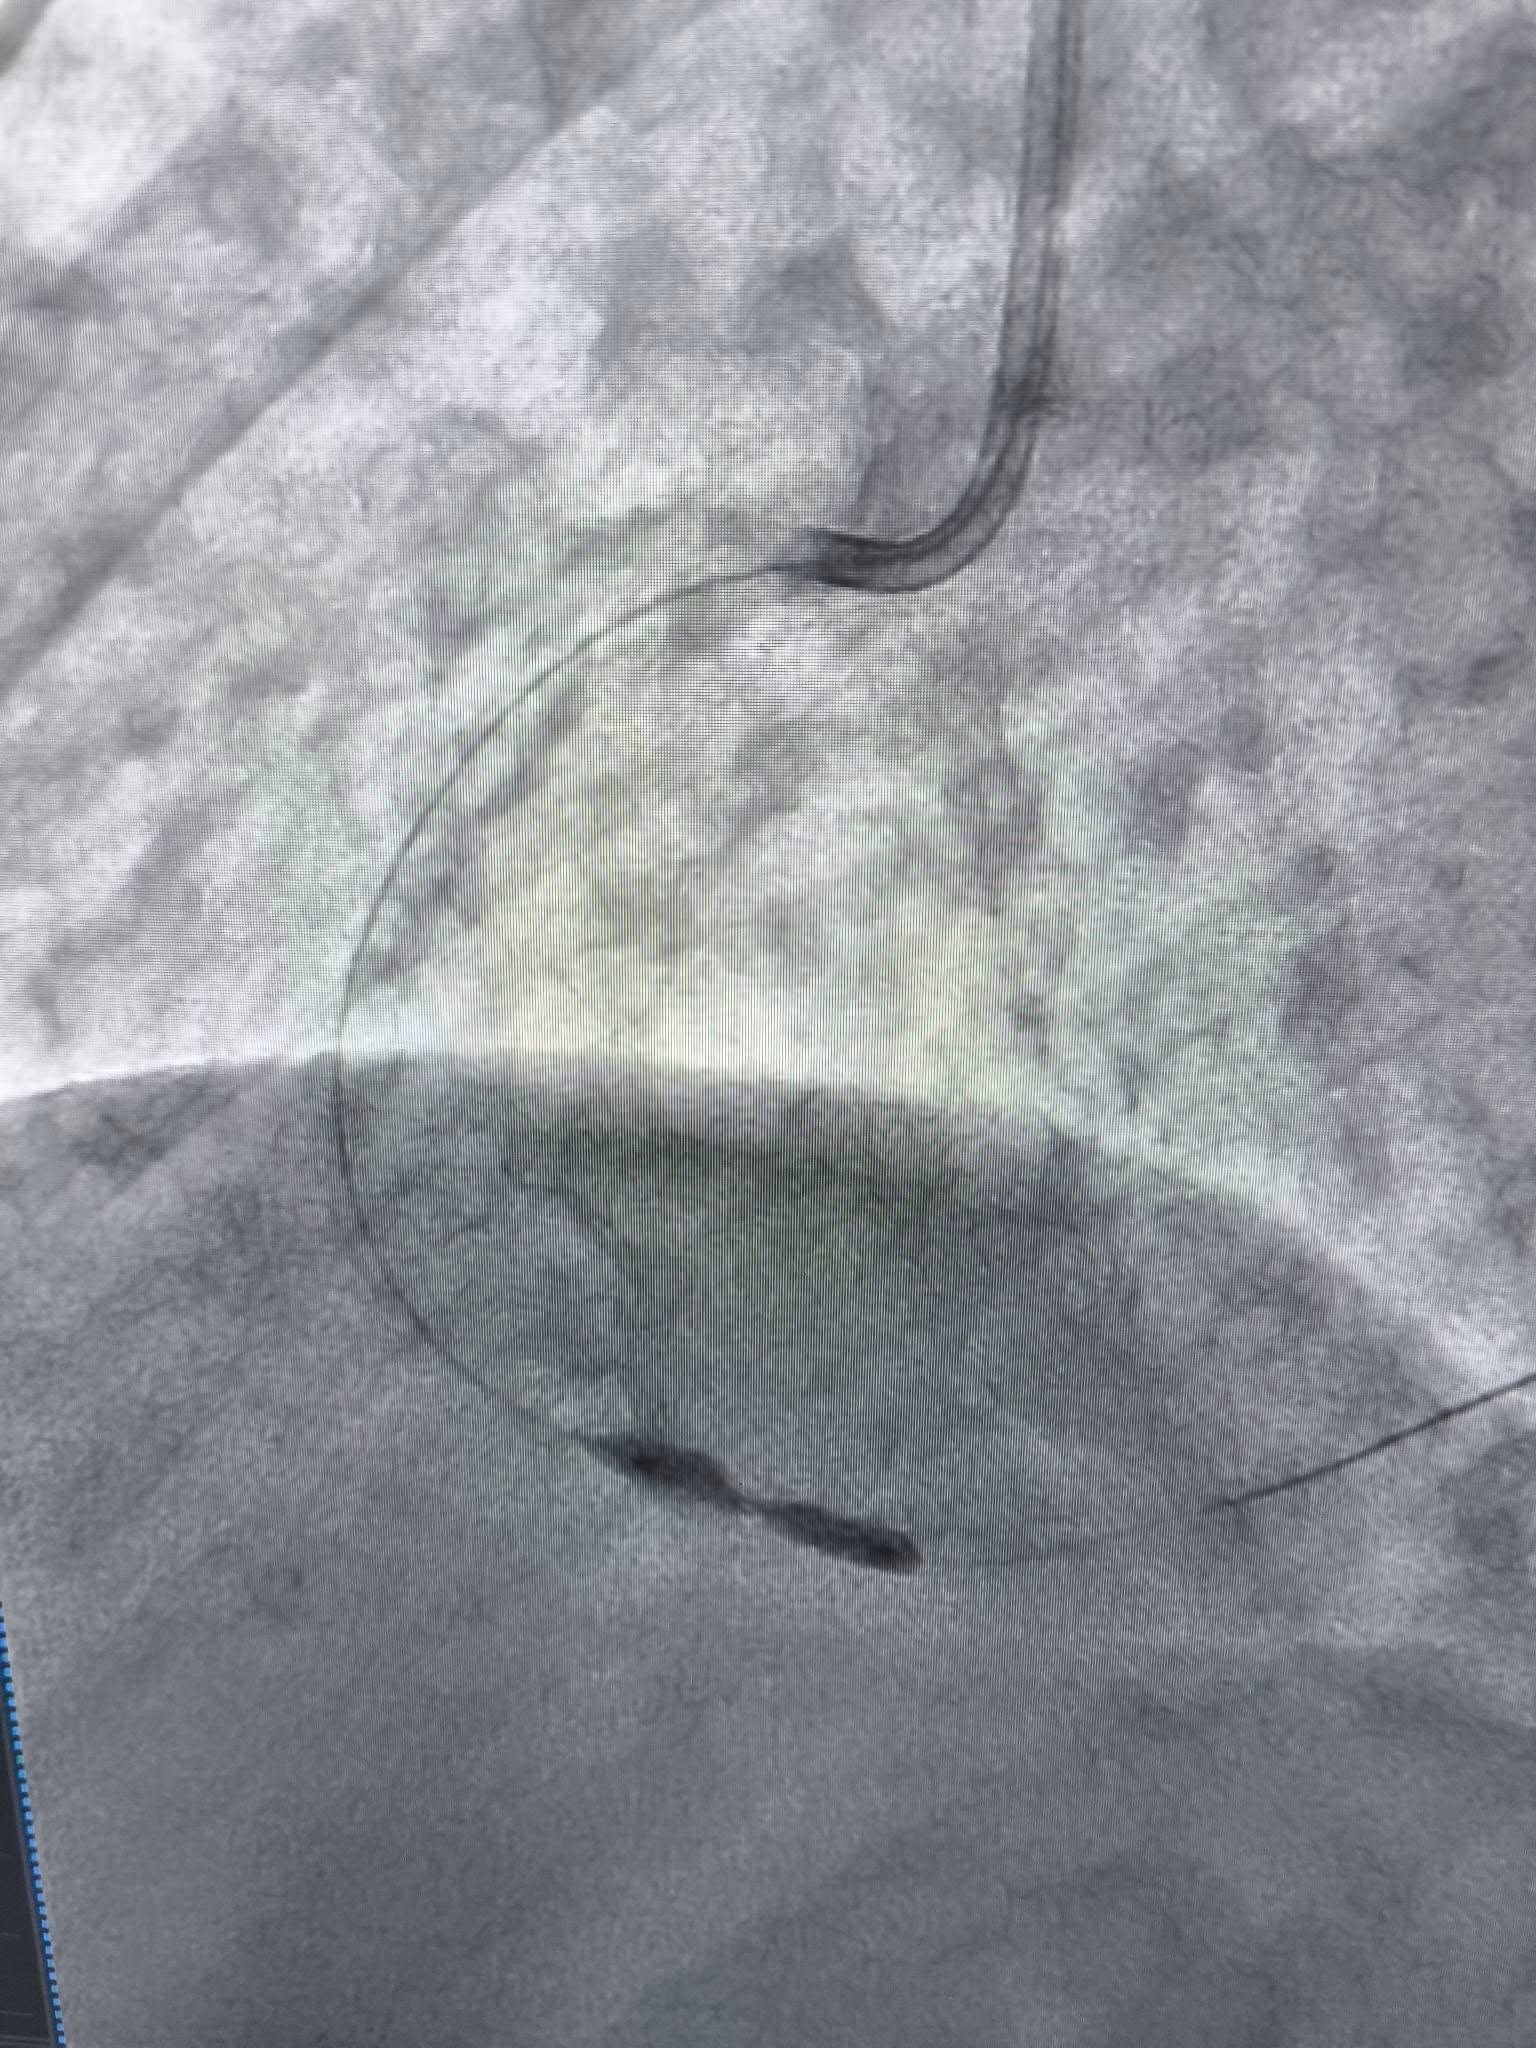

Єдиним виходом стало застосування ротаблятора – пристрою з крихітним буром, що має діамантове напилення.

- Бур обертається з величезною швидкістю, фактично «шліфуючи» кальциновану бляшку зсередини.

- Процедура модифікує структуру судини, роблячи її знову еластичною.

- Після «шліфування» лікарі отримують можливість безперешкодно встановити стент, який відновить нормальний кровотік.